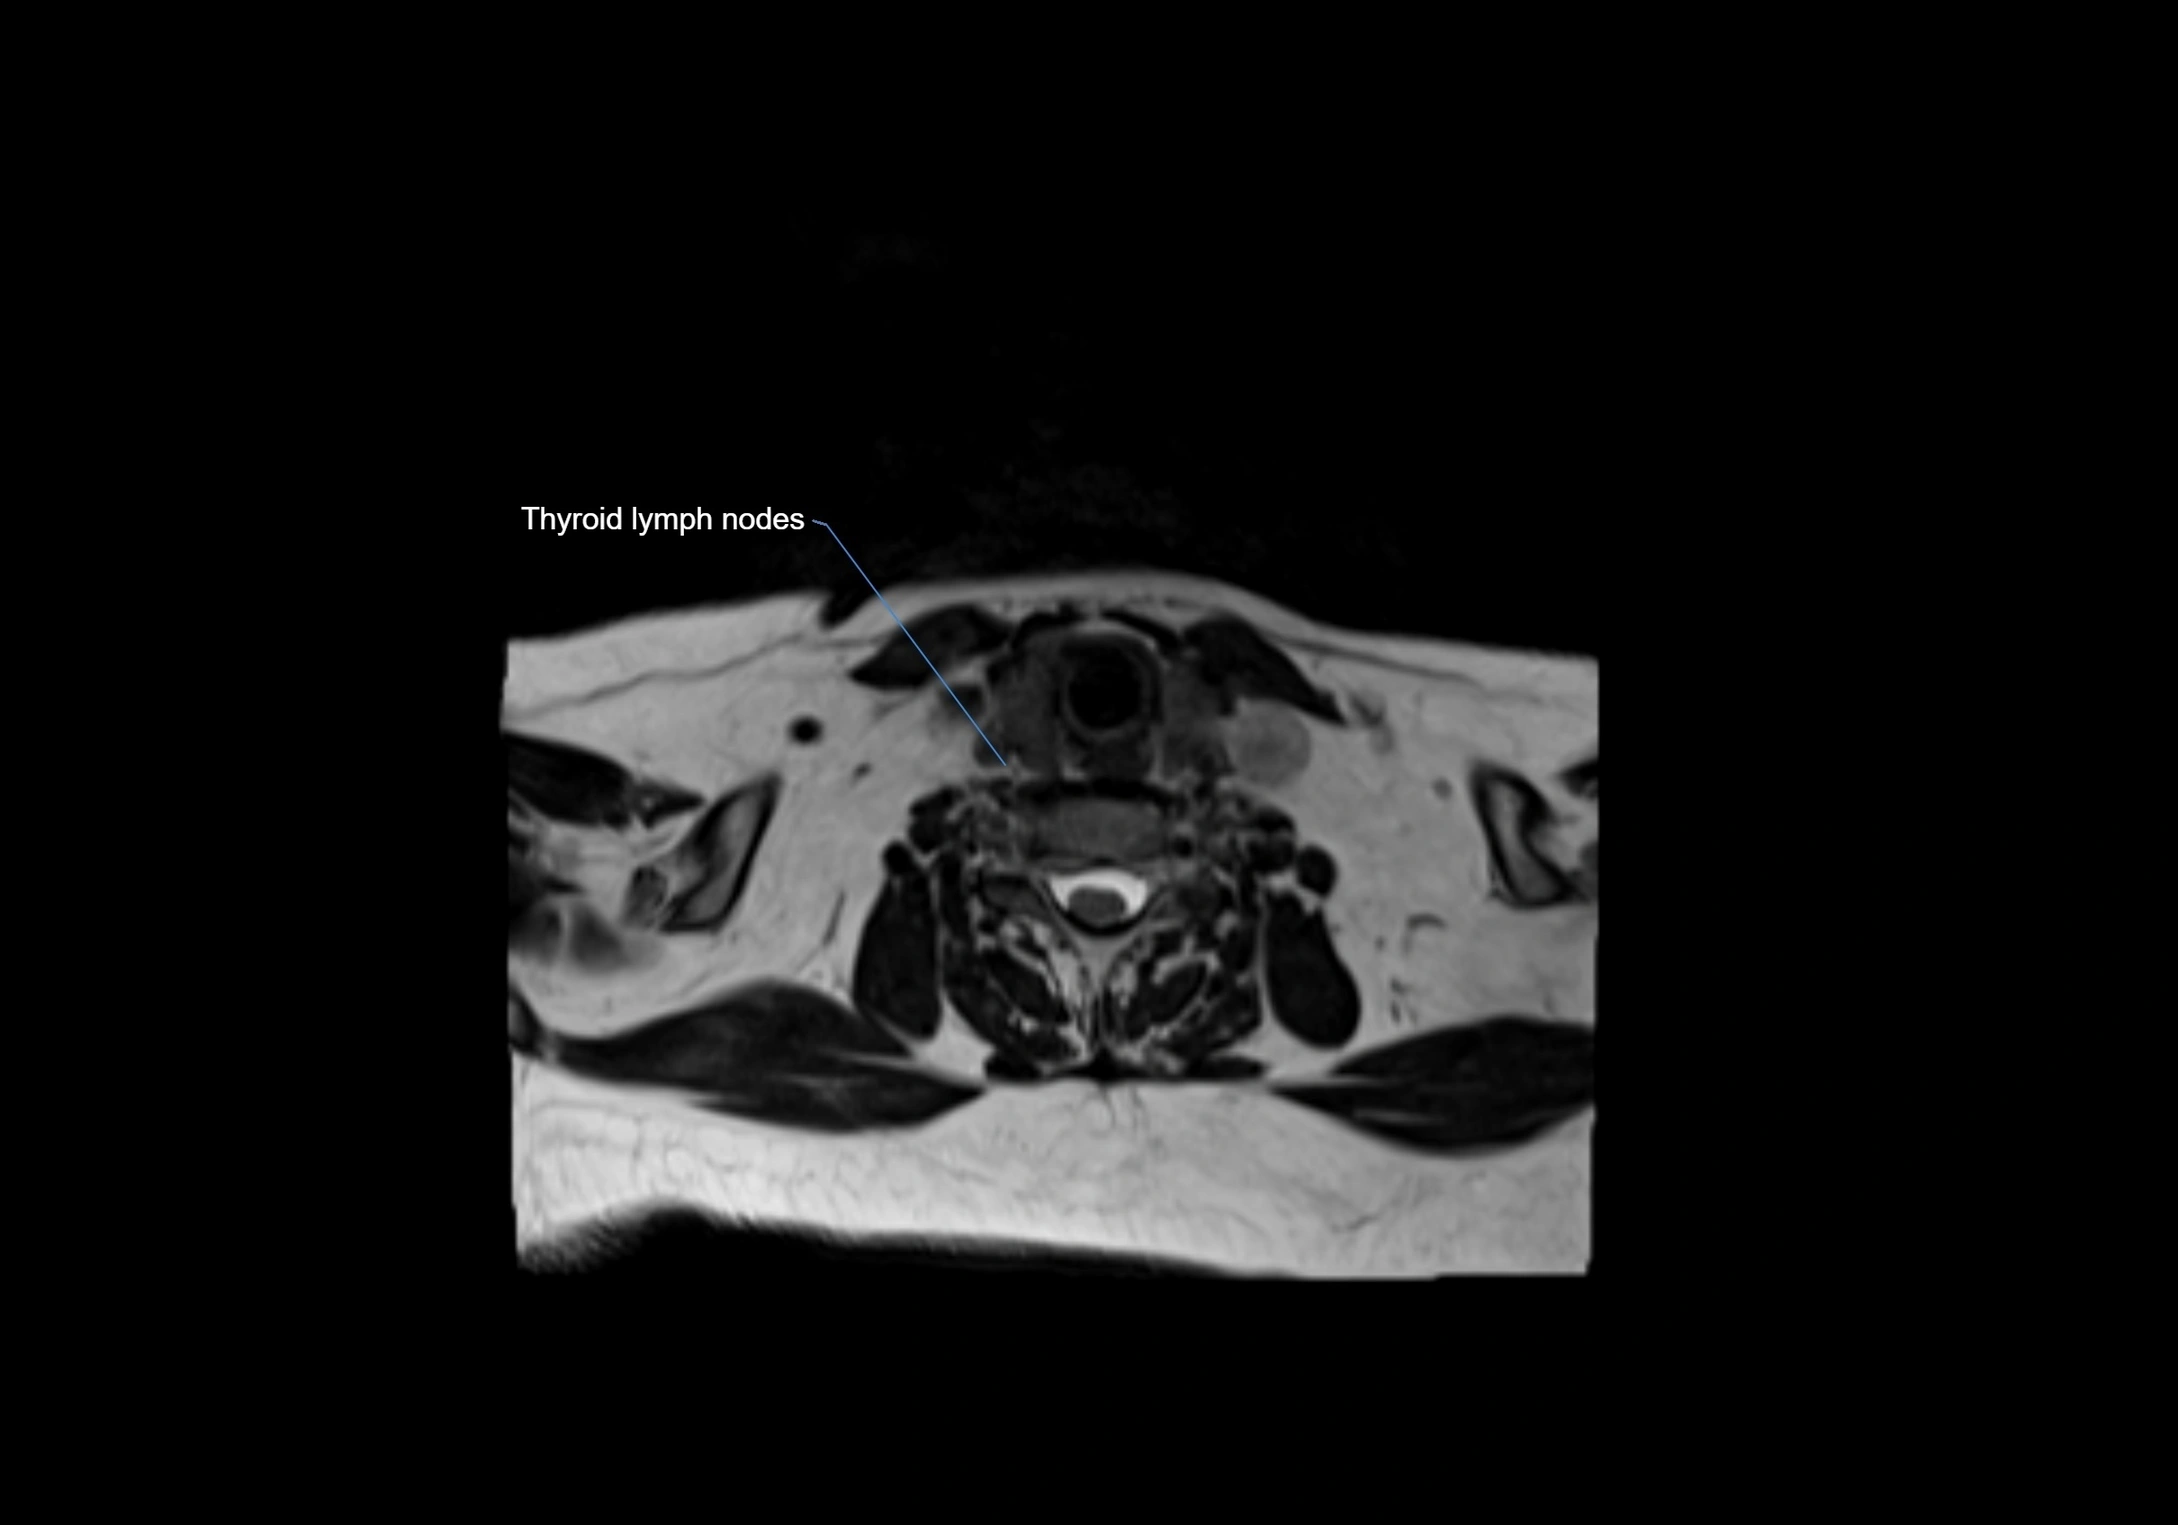

Location

• Found along primary lymph node chains, including preauricular, submandibular, parotid, and occipital regions

• Embedded in subcutaneous fat or superficial fascia, often lateral or posterior to primary nodes

MRI Appearance

MRI images

image